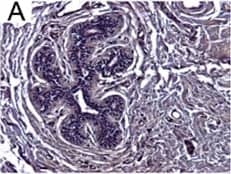

Detection of Human IL-6 by Immunohistochemistry

Breast DCIS cells overexpress proinflammatory markers. Representative images of immunohistochemistry targeting IL-6 protein in normal breast tissue (a), and breast DCIS (b) (N = 61). c and d Hematoxylin staining of serial sections from tissue shown in panel A and B. All images are 20X magnification. Scale bar equals 100 μm. e Evaluation of IL-6 gene expression in DCIS cells via qRT-PCR; the isogenic MCF10.DCIS cells and the non-isogenic SUM102 cell line were analyzed against the non-transformed MCF10A cell line (N = 3). f Secretion of IL-6 protein from DCIS cell lines and non-transformed MCF10A cells as determined by ELISA. *P < 0.05, Student’s t-test; mean ± SD Image collected and cropped by CiteAb from the following publication (https://pubmed.ncbi.nlm.nih.gov/26268945), licensed under a CC-BY license. Not internally tested by R&D Systems.